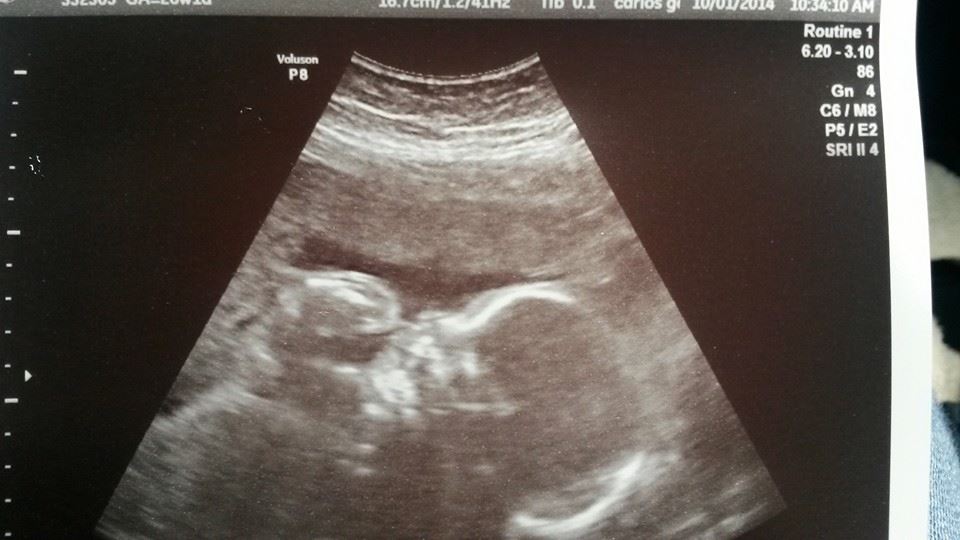

AWWWW.... my little girl is a toe sucker!

Went to the OB today for my regular appointment and she wanted to start growth scans because I haven't gained that much weight (this child eats EVERYTHING).  During the scan, this little girl pulls her leg up and starts sucking her toes!  I was overwhelmed with cuteness and had to share!